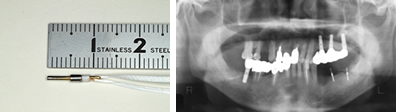

1.CFキャリパー

商品コード: 09-901-06 CFキャリパー右用 , 09-901-07 CFキャリパー左用

CFキャリパー右用 (下顎右側舌側の骨壁の厚さを予測するために使用する)

2.CTキャリパー

商品コード: 09-901-01 CTキャリパー右用 ,09-901-02 CTキャリパー左用

CTキャリパー右用 (下顎右側舌側の骨壁の厚さを実測するために使用する)